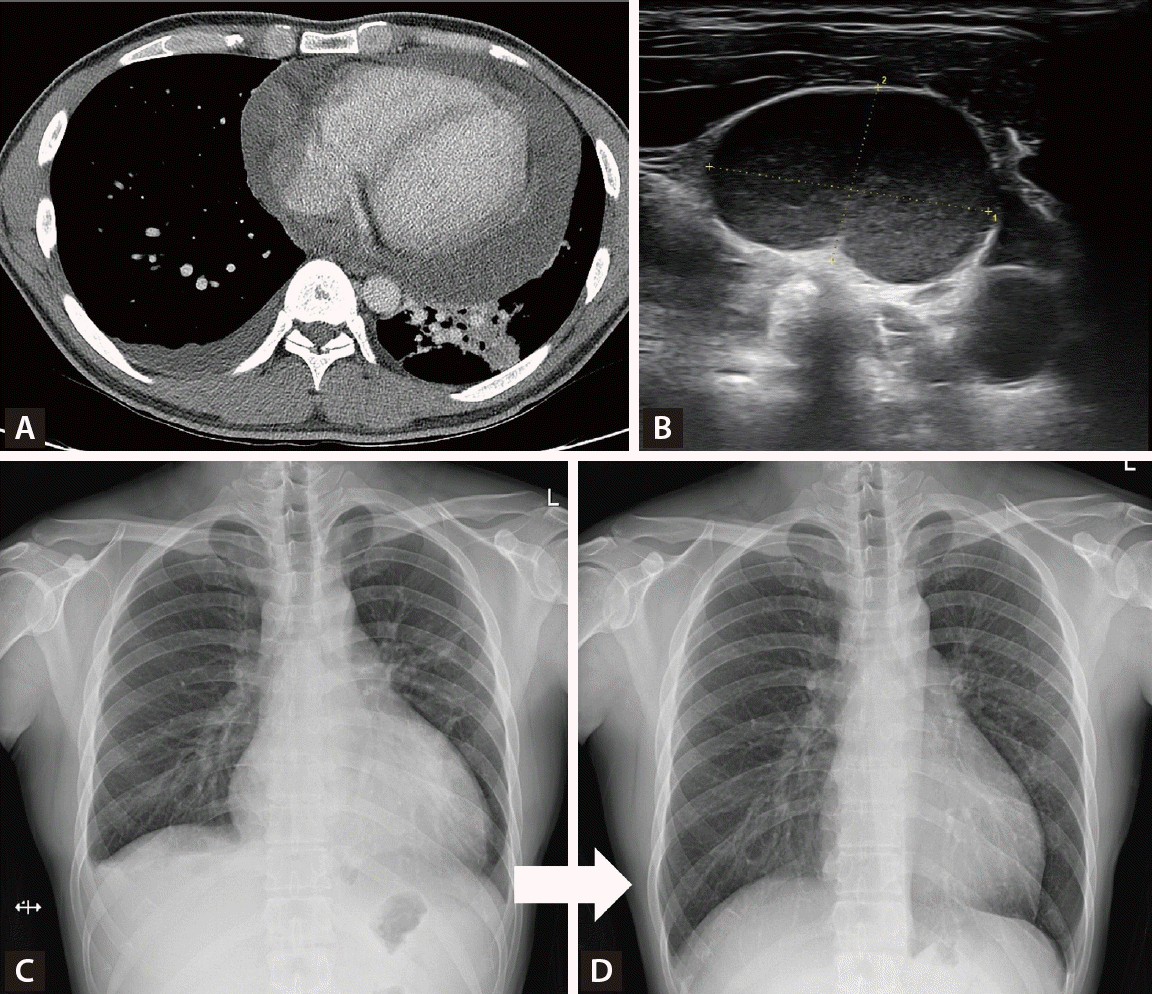

However, the patient developed persistent cough, dyspnea, and shortness of breath over one month, showing no improvement with conventional management, along with several palpable cervical lymph nodes. Chest computed tomography revealed a large pericardial effusion with impending tamponade physiology and diffuse parenchymal infiltration in the left lung field (Fig. 2A). Ultrasound-guided biopsy of the cervical lymph nodes revealed granulomatous inflammation with necrosis (Fig. 2B). Pericardiocentesis drainage was performed, showing positive AFB with M. tuberculosis culture, and adenosine deaminase (ADA) 11.3 IU/L, which was compatible with tuberculous pericarditis, and IGRA result were positive. Standard anti-tuberculosis medication (HREZ) was initiated for six months with rapid symptom improvement (Fig. 2C, D).

Figure 2.

(A) Chest computed tomography findings. On axial view, massive pericardial effusion with left lower lung infiltration were seen. (B) Neck ultrasound findings. About 2.1 cm-sized enlarged lymph node was seen. (C) Initial X-ray findings. Cardiomegaly due to pericardial effusion and pleural effusion were seen. (D) Follow-up X-ray findings. One month after pericardiocentesis, pericardial effusion was completely disappeared.